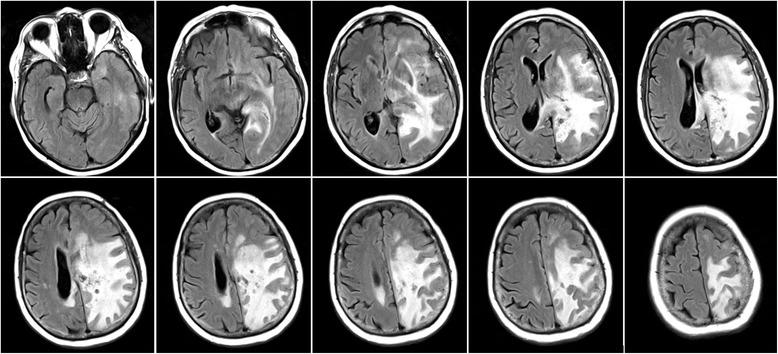

Here we report a case of an adult-onset LCC of a Caucasian woman who became symptomatic at age 70 as confirmed by typical neuroimaging and neuropathological findings. After resection of left mesioparietal space-occupying cystic brain tissue the patient has so far remained clinically stable during one year of follow-up with a continuous treatment with glucocorticosteroids.

我们在此报告一例成年发病的 LCC 病例,一名 70 岁的白种女性出现症状,典型的神经影像学和神经病理学检查结果证实了这一诊断。切除左中顶叶占位性囊性脑组织后,患者在接受糖皮质激素持续治疗的一年随访期间临床症状一直保持稳定。